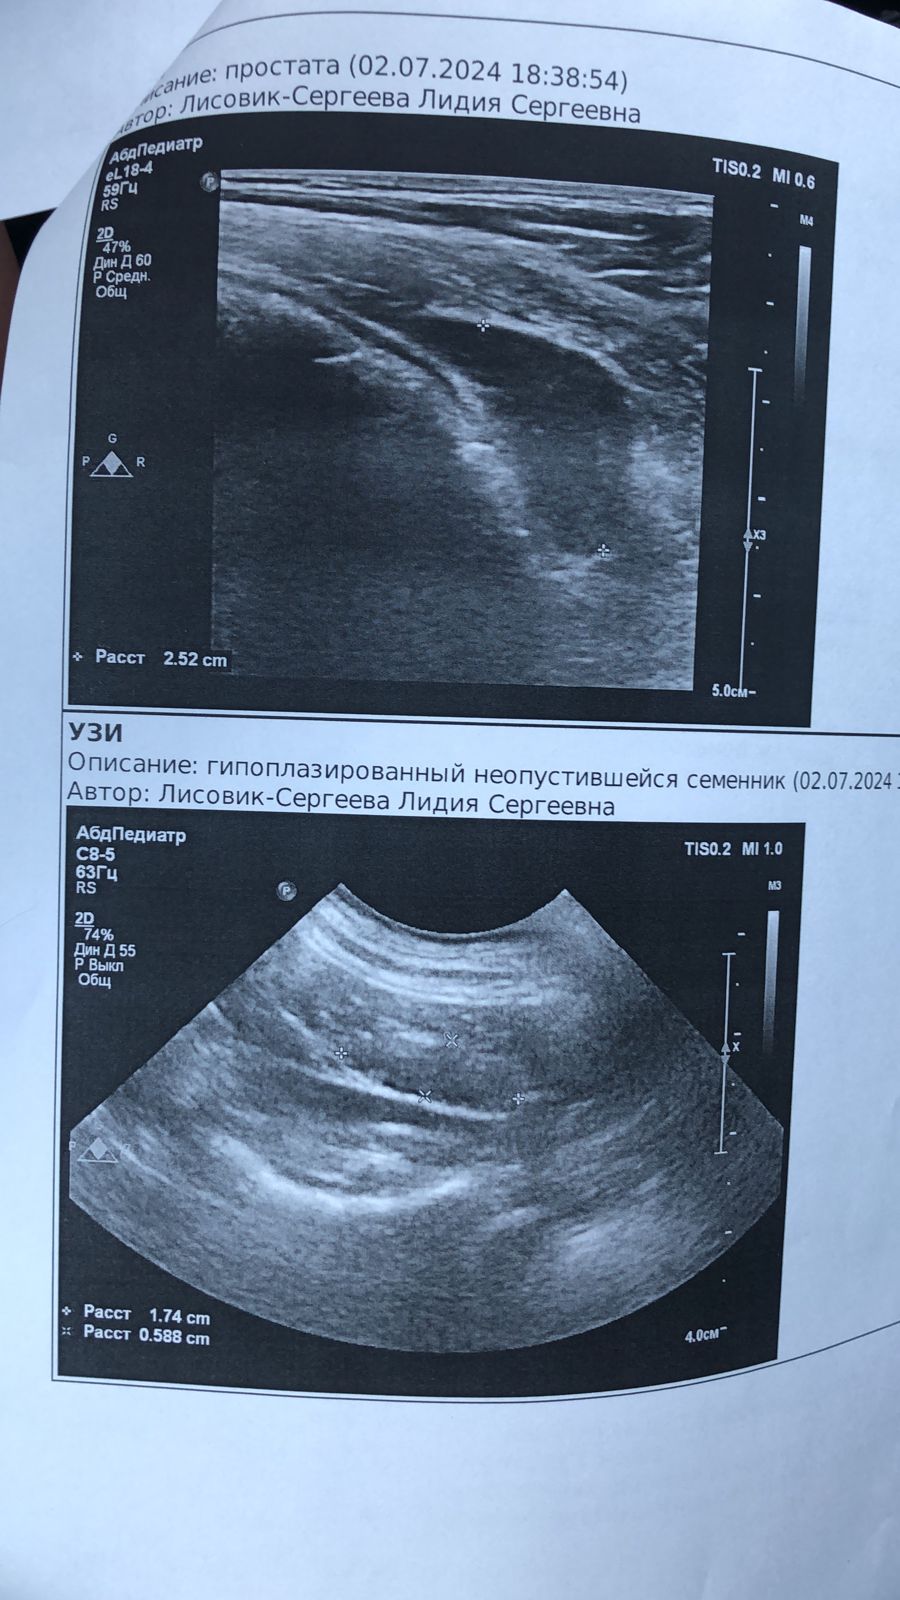

Поездка к онкологу и на УЗИ

IMG-20240702-WA0025.jpg

IMG-20240702-WA0023.jpg

IMG-20240702-WA0024.jpg

IMG-20240702-WA0022.jpg

IMG-20240702-WA0021.jpg